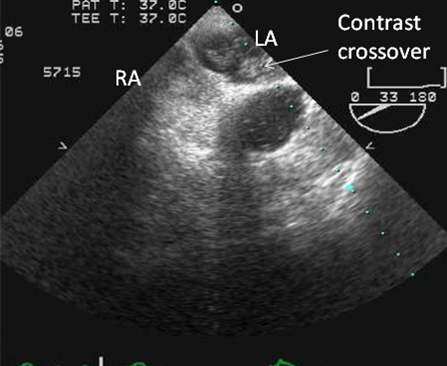

Performed in cases where a definitive diagnosis is sought; the transthoracic echo is either equivocal or negative; there is uncertainty as to whether the patient has atrial septal defect or PFO; and diagnosis is likely to alter management. [Figure caption and citation for the preceding image starts]: Transesophageal echo showing a 2D image of the interatrial septum with location of the PFOFrom the collection of Kul Aggarwal, MD [Citation ends].com.bmj.content.model.Caption@25b1fe2f[Figure caption and citation for the preceding image starts]: Transesophageal echo with intravenous injection of agitated saline showing contrast crossing through PFO into left atriumFrom the collection of Kul Aggarwal, MD [Citation ends].com.bmj.content.model.Caption@6d238800[Figure caption and citation for the preceding image starts]: Transesophageal echo with color flow Doppler showing presence of PFOFrom the collection of Kul Aggarwal, MD [Citation ends].com.bmj.content.model.Caption@2446563

visualization of defect, color flow at the interatrial septum and crossover of microbubbles from right atrium to left atrium after intravenous injection of agitated saline